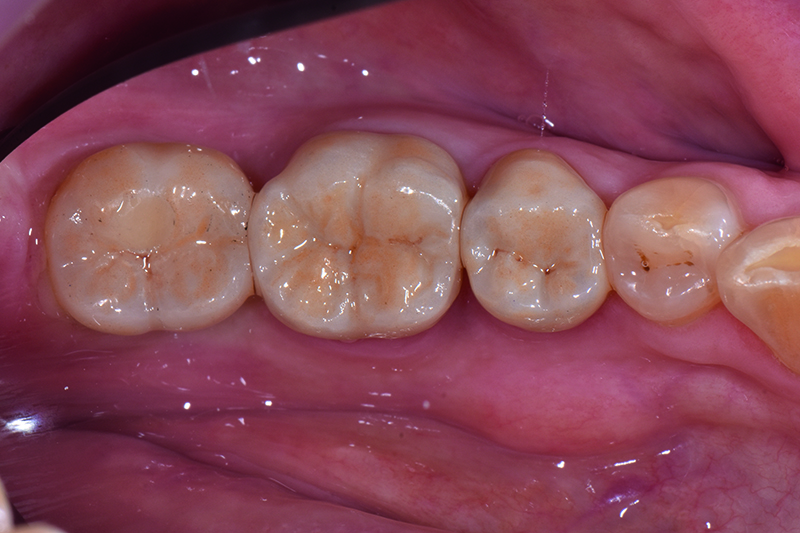

Cas clinique avec Initial™ LiSi Block

Initial™ LiSi Block est disponible en haute translucidité (HT) et en faible translucidité (LT). Il offre une opalescence naturelle sous toutes les lumières.

Restauration en Initial™ LiSi Block sous lumière directe et indirecte.